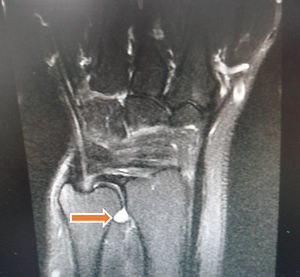

Reporte de casoAsiste a la consulta una paciente de 58 años, diestra, ama de casa, quien refiere que su cuadro clínico tiene tres años de evolución con dolor en la región cubital de la mano derecha, que desde hace dos meses se ha intensificado extendiéndose hasta la región radial. Lo asocia con edema en puño y dorso de la mano con las actividades repetitivas, sensación de parestesias en la región interdigital y pérdida de fuerza. La paciente relaciona el inicio de la sintomatología con una lesión por agresión en la que le apretaron y estiraron la mano. Indica que un médico particular le realizó infiltraciones de «plasma rico en plaquetas» dos años atrás con mucha mejoría de la sintomatología. Al examen físico se encontró dolor en el lado cubital del puño en el trayecto del extensor carpi ulnaris, que se exacerba con la extensión del puño, sin inestabilidad dorsal o palmar de la articulación radiocubital distal. No hay signo de la tecla, pronosupinación no dolorosa, fuerza 5/5 bilateral y sensibilidad conservada. Los estudios que aporta incluyen neuroconducción de hace 3 años, cuyo resultado es normal y resonancia magnética reciente que muestra ganglión del intervalo radiocubital distal de 14x14x5mm (figs. 1 y 2).